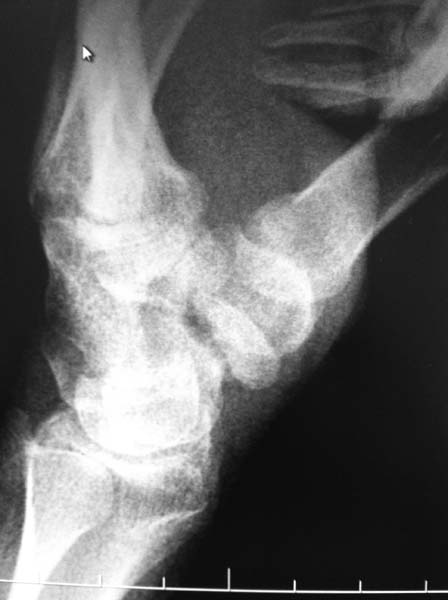

Уважаемые коллеги! Выскажете свое мнение по тактике лечения. Пациент 21год, обратился через 6 месяцев после травмы с жалобами на ограничение движений и боль в области кистевого сустава. На рентгенограммах видно, что размер дистального отломка ладьевидной кости невелик, в связи с чем возникает вопрос: есть ли смысл делать аутопластику костным штифтом или показано удаление дистального отломка? Сомнения возникли в связи с возможными техническими трудностями (вероятность расколоть столь малый отломок при формировании канала), да и вообще перспектив сращения такого рода ложного сустава. Заранее благодарен за ответы. С уважением.